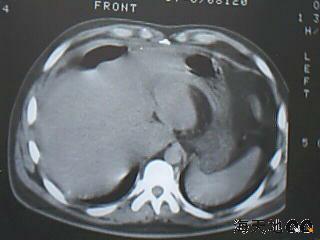

男 32y 外伤后一月余,现 t38.5,肝区隐痛。

右肝膈顶区液气平面.右膈肌增厚改变,病灶下部层面呈半月形延伸于肝表面.且于横结肠无明确密度切关系.

结合临床症状;考虑膈下脓肿.建议薄层矢状重建进一步证实.

鉴别;1,膈疝;2,间位结肠.

右隔肌与肝顶之间隙有长气液平,其下散在点状气体影,右侧腹膜局限增厚。考虑右膈下脓肿。

考虑右膈下脓肿。病灶不在肝内,位于肝外膈下;病灶下方的层面无结肠影与之相连。

右膈肌增厚,肝膈间见条状低密度影内可见积气影及宽大液平面,并未见与结肠相连。因此考虑膈下脓肿。